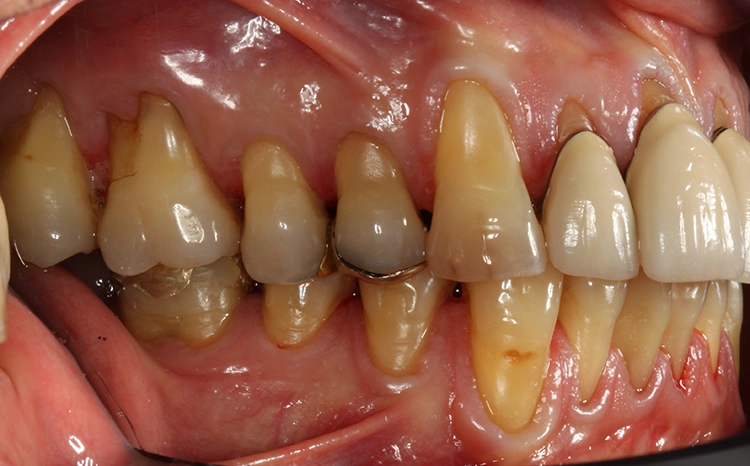

Die manuelle und klinische Funktionsanalyse ließ auf eine parafunktionelle Aktivität schließen. Es zeigten sich generalisiert Erosioabrasionen und Attritionen mit zum Teil freiliegenden Dentinarealen. Es lagt eine Angle-Klasse II/1 vor. Die manuelle Führung ergab keine Abweichung in maximaler Interkuspidation (ohne Führung) und zentraler Kondylenposition (mit Führung) (Tab. 1). Keine Krepitationsgeräusche der Gelenke, unauffällige Öffnungs- und Schließbewegung, keine Druckdolenzen der Muskulatur bei Palpation. Der Patient berichtete von gelegentlichen leichten Kopfschmerzen.

Egger/Wermuth/GrevenRote Ästhetik: Im Ober- und Unterkiefer zeigten sich generalisiert ausgedehnte Rezessionen mit bis zu 8 mm Attachmentverlust vor allem im Bereich der Eckzähne (Miller-Klasse III; Rezessionstyp [RT] 2 [69]. Das Band an keratinisierter Schleimhaut ist durchgehend vorhanden. Die Breite variiert im Eckzahnbereich von 1 mm bis zu 2 mm im Bereich der Unterkieferfrontzähne, der Prämolaren und Molaren (Abb. 1). Die fazialen Rezessionen sind mit approximalem röntgenologischem Attachmentverlust im koronalen Wurzeldrittel (Abb. 2) und Papillenverlust im Bereich zwischen den Kontaktpunkten und der approximalen Schmelz-Zement-Grenze assoziiert (Abb. 1). Der Patient verfügt über eine schmal geformte Oberlippe. Die Lachlinie verläuft mittelhoch (Abb. 3).

Dentalstatus: Es zeigen sich generelle Abrasionen, Attritionen und Erosionen im Ober- und Unterkiefer. Die ursprüngliche anatomische Kauflächenstruktur in den Seitenzahnbereichen ist durch die massiven erosions- und attritionsbedingten Zahnhartsubstanzverluste nicht mehr vorhanden (Tab. 2). Aufgrund der massiven Zahnschmelzverluste erscheint die Zahnfarbe insgesamt gelblicher. Der Patient wünscht sich im Rahmen der Rehabilitation in dieser Frage eine merkliche Verbesserung.

Egger/Wermuth/GrevenBefunde

Parafunktion mit massivem Zahnhartsubstanzverlust (Erosioabrasionen und -attritionen vor allem im Okklusalbereich) bei bestehender Klasse II/1 Verzahnung. Generalisierte parodontale Rezessionen vor allem im Bereich der Eckzähne (Miller-Klasse III; RT 2). Störung der statischen und dynamischen Okklusion (fehlende Eckzahnführung). Gelegentliche leichte Kopfschmerzen, prothetisch und konservierend insuffizient versorgtes Erwachsenengebiss.

Parodontale Gesundheit bei Attachmentverlust, Bruxismus, Erosion. Abbildung 1 sowie 6 bis 9 zeigen den Anfangsbefund als intraoralen Fotostatus.*